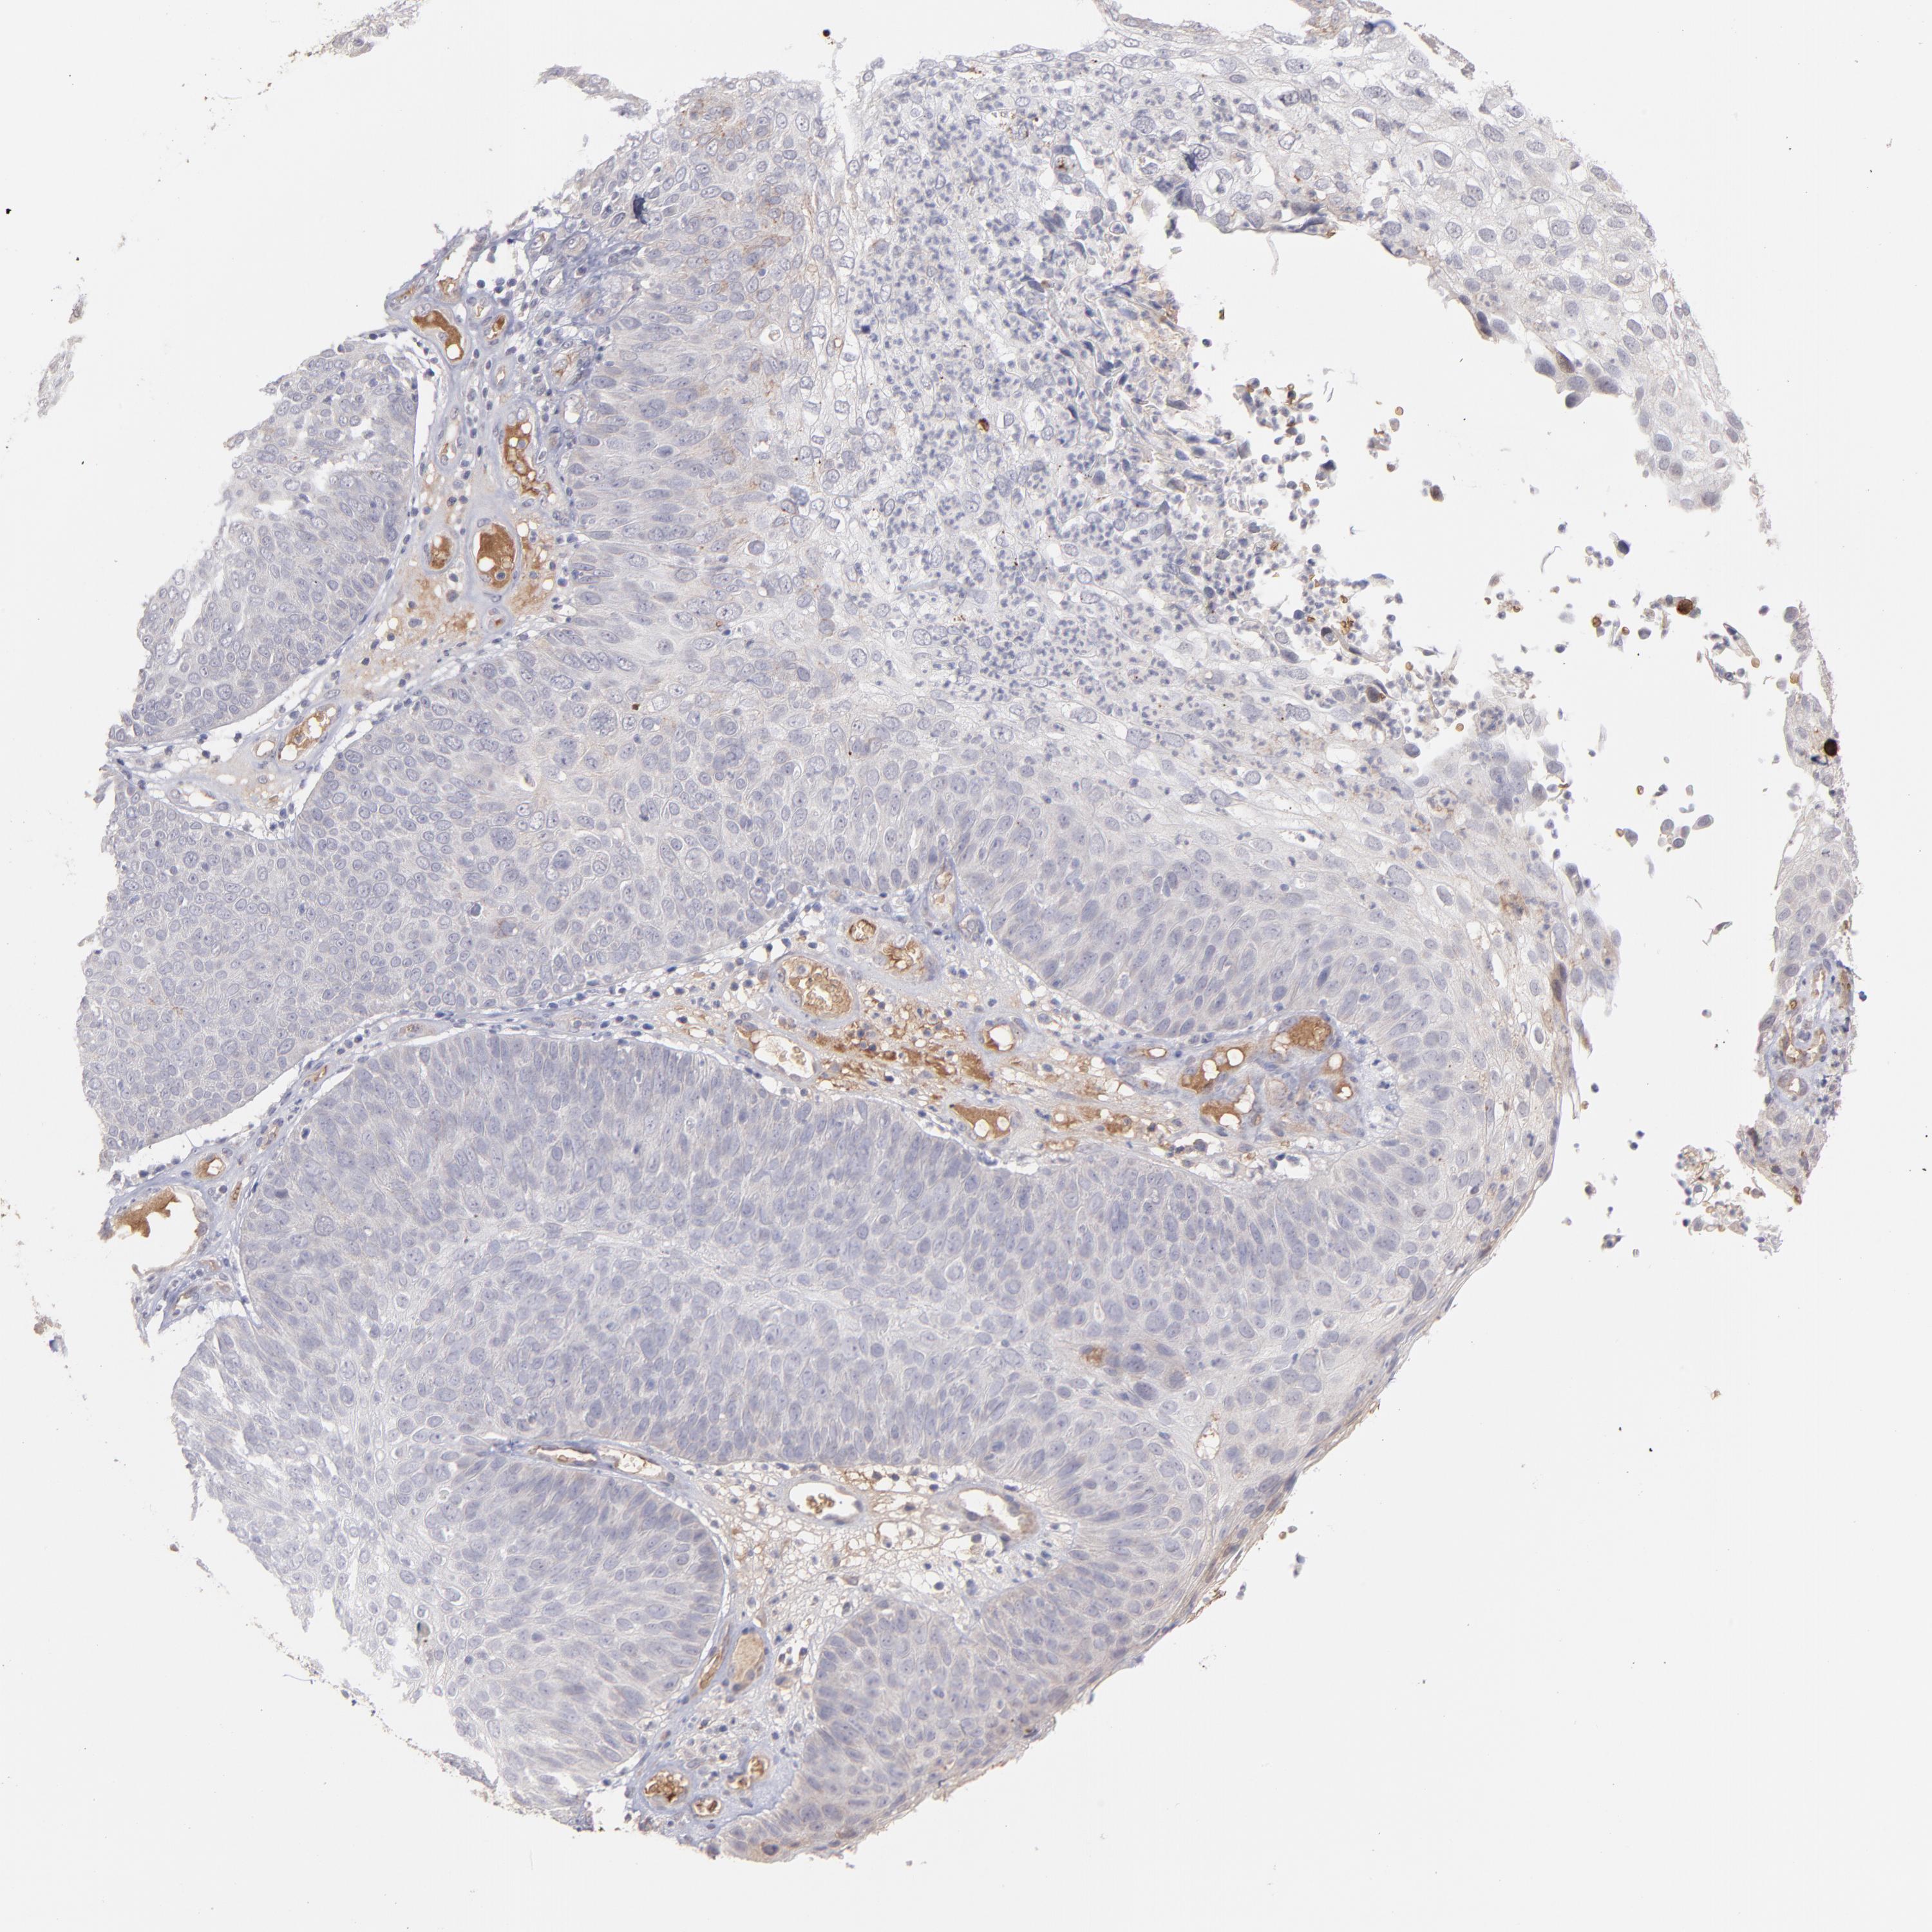

Basal cell and squamous cell cancer

SKIN CANCER - Protein expressioni

A mouse-over function shows sample information and annotation data. Click on an image to view it in a full screen mode. Samples can be filtered based on level of antibody staining by selecting one or several of the following categories: high, medium, low and not detected. The assay and annotation is described here.

Antibody stainingi

Antibody staining in the annotated cell types in the current human tissue is reported as not detected, low, medium, or high, based on conventional immunohistochemistry profiling in selected tissues. This score is based on the combination of the staining intensity and fraction of stained cells.

Each image is clickable and will lead to virtual microscopy that enables deeper exploration of all samples and also displays staining intensity scores, fraction scores and subcellular localization as well as patient and tissue information for each sample.

Antibody HPA003827

Squamous cell carcinoma, NOS